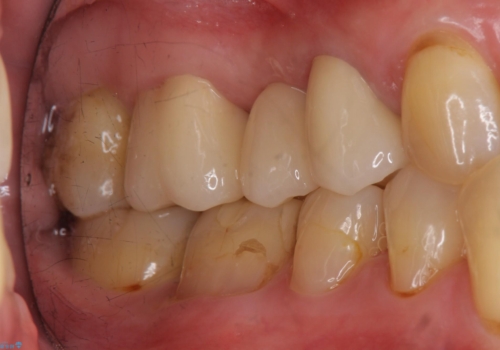

奥歯が割れてしまった インプラントでかめるように 全体的な治療も

- 右下の奥歯が割れてしまい、抜歯を行いました。

ブリッジにできない位置であったため、インプラントでかめるようにしました。

また、向かい合う上の歯が挺出(伸び出してしまうこと)しており、インプラントを入れることが難しかったため、長さを短くかぶせ治しました。

また、上顎前歯以外の根の治療のやり直しを行いました。

上顎前歯は他院で根管治療とセラミックを行なったとのことで、歯肉縁下形成のため、歯肉の腫れが治りにくい状況でしたがやり直しは希望されませんでした。

左下に関しては、経過観察を行い、歯が割れたりした場合にインプラントを考えることになりました。